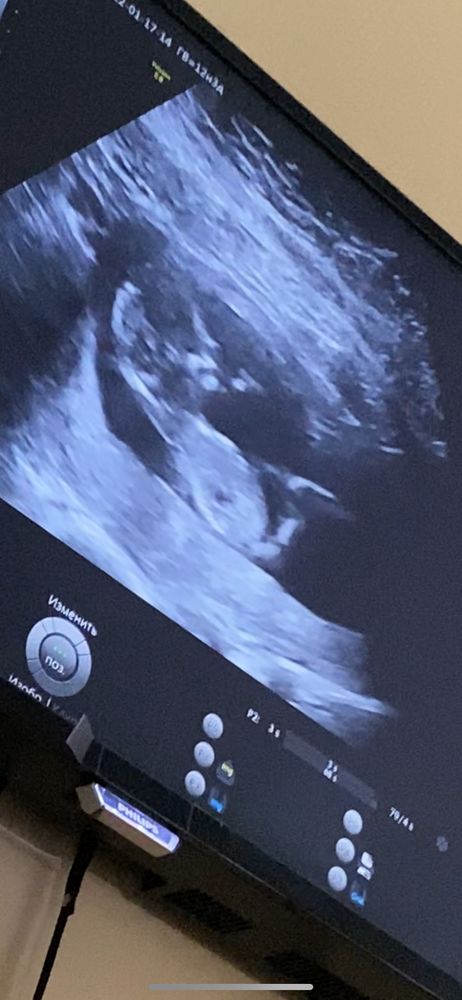

жду девочку, 15 неделя Балаково

Первый скрининг 🥳

На фото не видно пол (нам сказали в 12 недель мальчик жду теперь 16 недель чтоб узнать точно )в 16 говорят точно хотя мне с первым как сказали мальчик так и бегает уже 5 лет сейчас конечно девочку хотелось но видимо снова парень ))но я почему то сама чувствую что мальчик )

Ну здесь к сожалению ничего не видно )